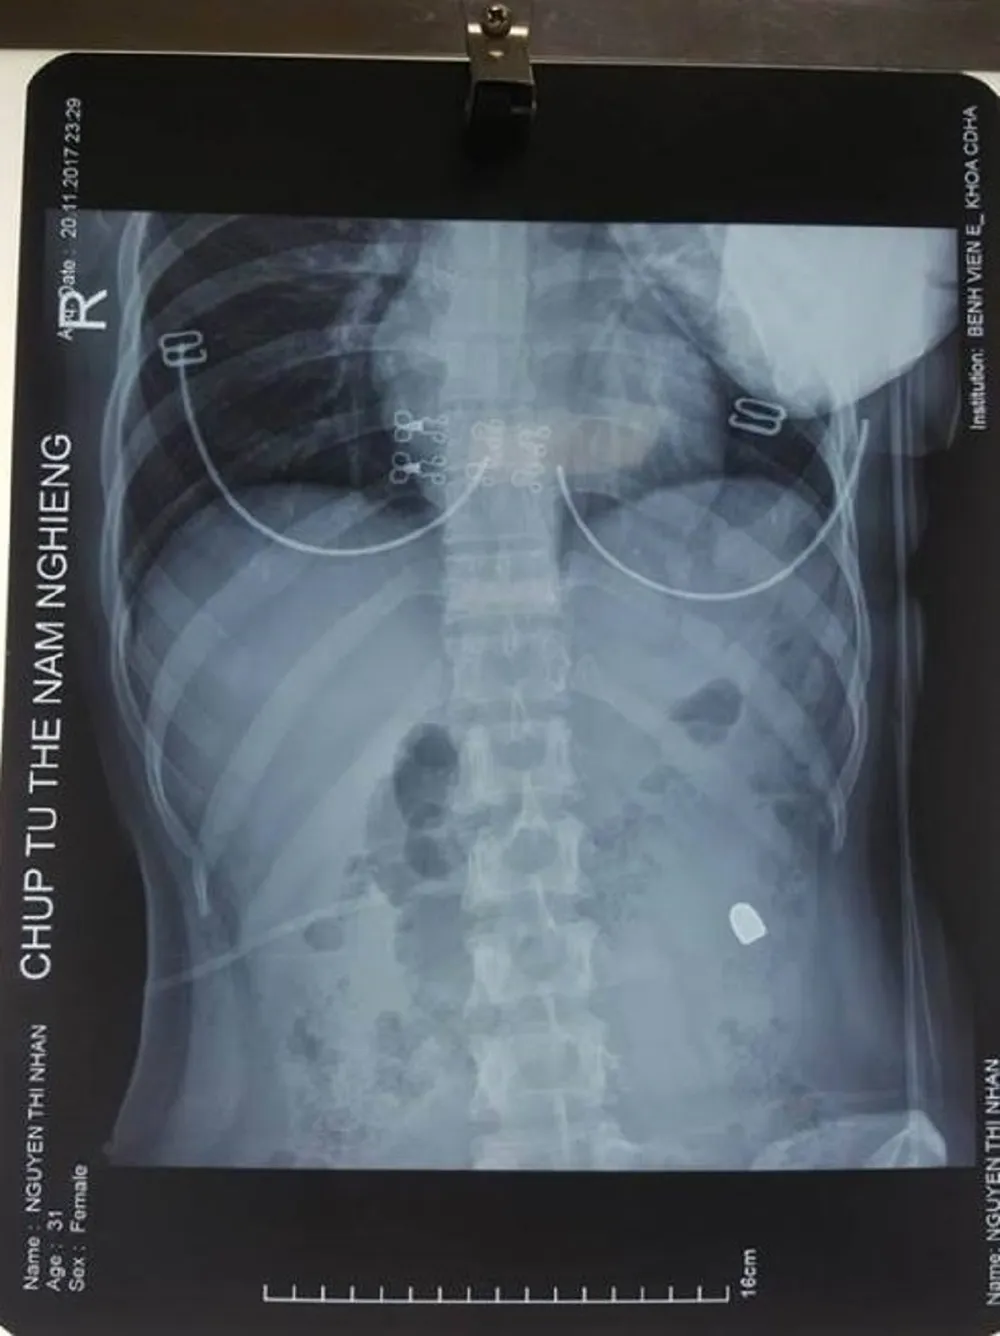

Viên đạn xuyên thủng vùng bụng của nạn nhân

Kết quả chụp X-quang cho thấy một đầu đạn nằm tại mạn sườn trái của bệnh nhân, cô được đưa lên phòng mổ.

Phim chụp Xquang cho thấy viên đạn nằm sâu trong bụng bệnh nhân